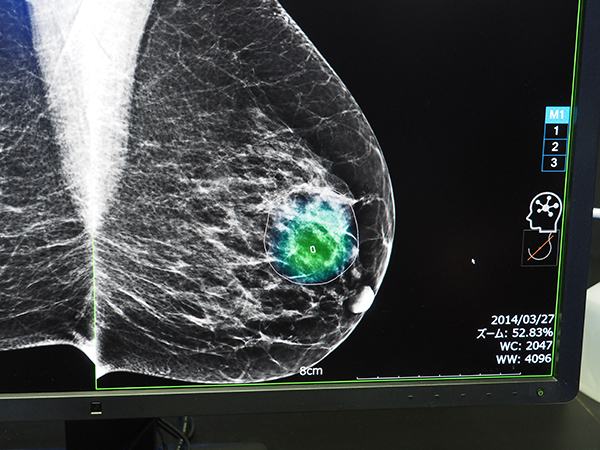

今回紹介されたINFINITT AI Platformは,マルチベンダーの画像診断解析ソフトウエアと接続し,DICOMデータを基に解析された結果をビューアやワークリストで表示する。疑わしい病変領域はヒートマップや輪郭で表示し,ワークリスト画面では,病変数や所見,陽性確率などが使用したAIソフトウエアなどとともに一覧で表示される。加えて,解析結果に基づいた検査の優先度を事前に設定し,表示する機能もある。検査種別や解析ソフトウエアごとの結果などをそれぞれの特性に合わせて取り込んで表示できるのが特長であり,画像解析AIの情報をフル活用できるソリューションである。韓国ではすでに多くの運用例があり,日本国内からの問い合わせも多いという。

疑わしい病変部領域は,ヒートマップと輪郭で示され,AI解析が行われた画像には脳のマークが表示される。